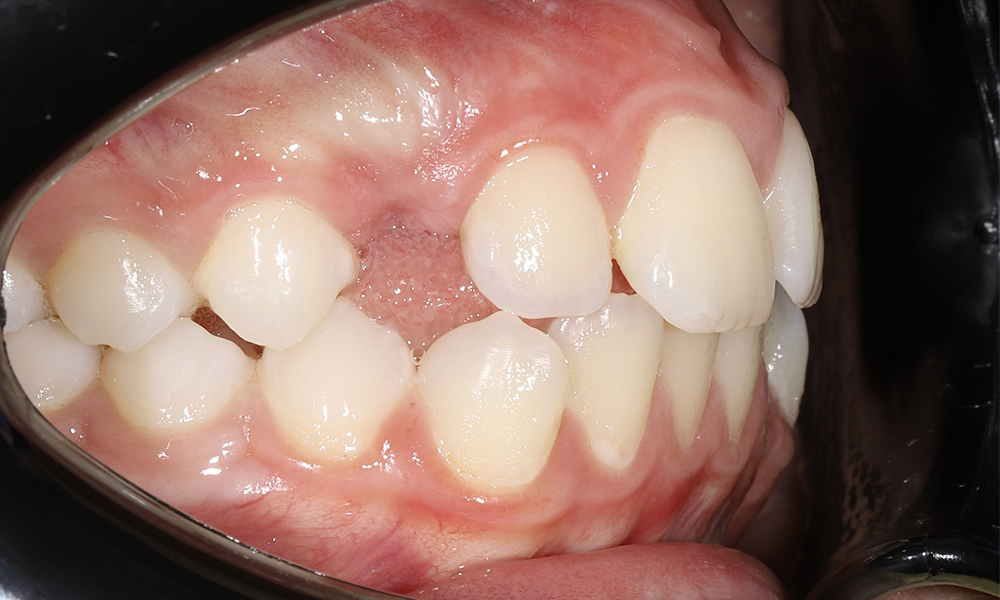

Ортодонтическое лечение с генерализованным пародонтитом